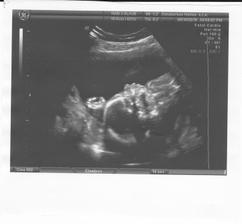

UTZ ve 20 tt 8.6. - odpovídáme 21+1 tt (trošku jsme vyrostli), vše v pořádku a mimi váží 400 g 😉

16.6. v 16:30 (skoro magické číslo 🙂) UTZ srdíčka - vše dopadlo výborně, žádná vrozená srdeční vada u miminka neprokázána....a čekáme ZDRAVÉHO chlapečka 🙂) obroská radost a úleva 🙂)